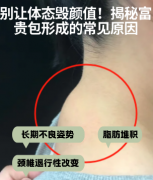

重庆超雅做富贵包是用什么技术?

长时间不良习惯,如低头玩手机、饮食不规律等都可能引起富贵包的。富贵包就是颈背部出现了脂肪堆积。不过啊,虽然它叫富贵包,却不是什么富贵的代表,我就因为这个富贵包得了<